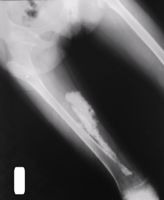

Medical imaging usually shows a well-defined wide-based bony growth on the surface of bone.[5] It can be pedunculated and irregular, giving it a "bizarre" appearance, and is not connected to underlying bone.[2]